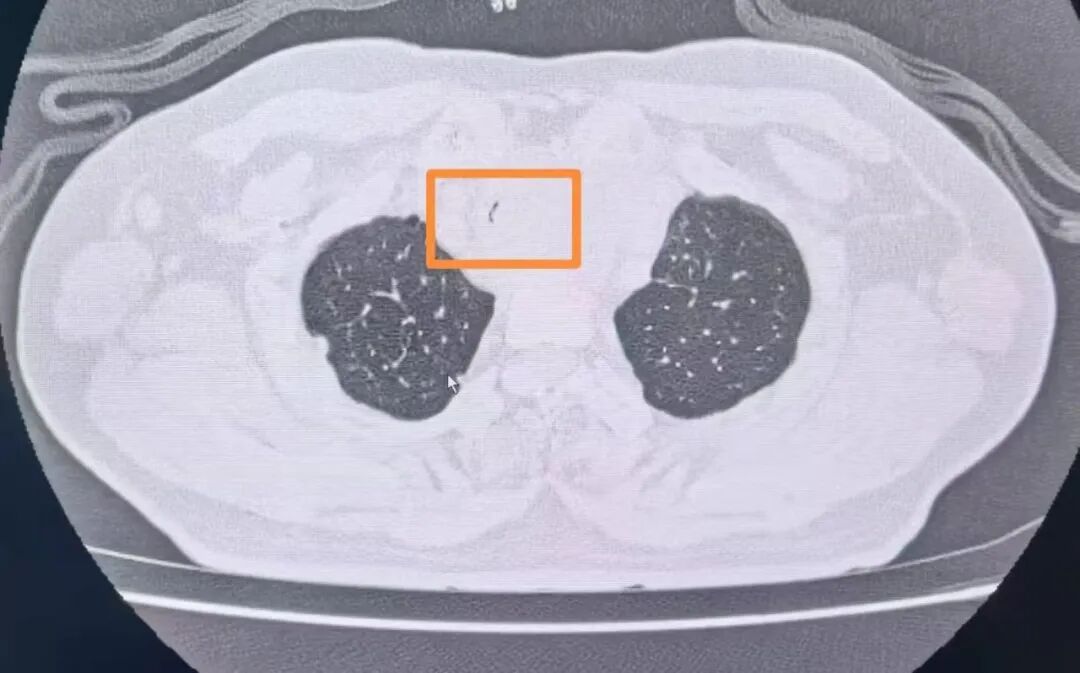

經(jīng)復(fù)查胸部CT發(fā)現(xiàn)患者氣管已經(jīng)出現(xiàn)明顯狹窄,內(nèi)徑最窄處直徑不到2mm(正常成年男性氣管內(nèi)徑為18-22mm),呈“一線天”樣改變,整個氣管僅靠一條細(xì)微的縫隙維持著少量的通氣,意味著病人隨時有發(fā)生窒息的危險。甲乳外科立即組織開展了多學(xué)科討論。經(jīng)過對病情的充分分析,呼吸與危重癥醫(yī)學(xué)科副主任陳暉建議緊急行氣管內(nèi)支架置入術(shù)解除大氣道梗阻。